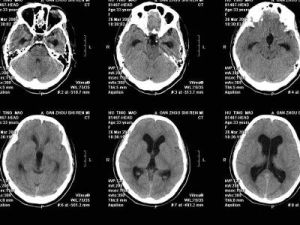

(1) 慢性顱內壓增高征,頭痛和噁心、嘔吐均較急性腦積水輕,眼底水腫常伴有繼發性萎縮。

(1)過度分流綜合徵 兒童多見。病人出現典型的體位性頭痛,直立時加重而平躺後緩解。CT檢查顯示腦室小。

(3)腦脊液分流不足 病人術後症狀不改善,檢查發現腦室擴大仍然存在或改變不明顯。主要原因是使用的分流管閥門壓力不適當,導致腦積水沒有治好。